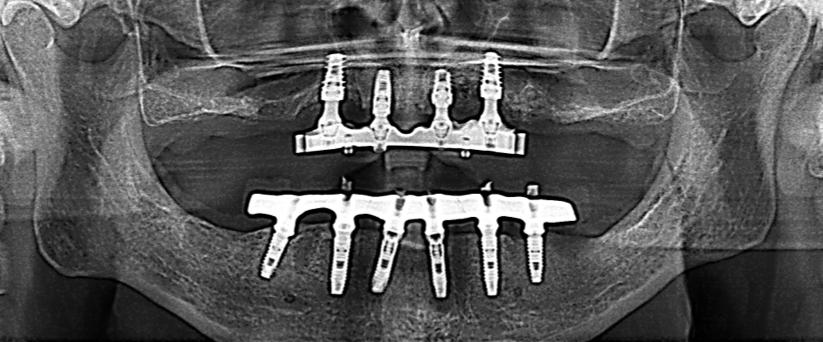

IMPLANTOLOGIA GUIDATA Chiavi in mano Per saperne di più contatta ora dentecom.srl@gmail.com

Rigenerazione ossea

Lettura digitale

Via Francesco Saverio Sprovieri, 35 - 00152 Roma (RM) T. +39 06 58330870 | +39 392 6060066 dentecom.srl@gmail.com - www.dentecom.it